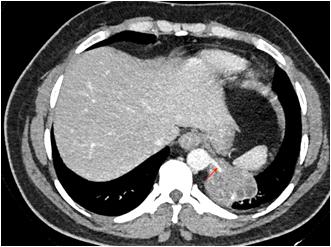

histopathology or polymerase chain reaction in a Patient with a clinical diagnosis of Invasive Mucormycosis. Cases were considered COVID-19 associated if the patient received a positive Reverse Transcription Polymerase Chain Reaction or Antigen test result for SARS-CoV-2 during the 60 days preceding the mucor diagnosis1.” Every patient is evaluated at presentation with detailed history, Clinical examination, ENT, Ophthalmic and Neurological examination to assess the extent of disease. Patients’ occupational history, personal habits, Socio-economic status (Modified B G Prasad Scale), prior treatment, vaccination status & COVID status were recorded at admission. Patients with pre-existing Facial Nerve palsy due to other known causes like cerebrovascular accident, non-covid intracranial, temporal bone, parotid pathology were excluded. Facial soft tissue involvement if mimicking Facial Palsy was also excluded. Facial Nerve function assessment was done in detail. It was first subdivided into upper and lower Motor Neuron type of deficit. LMN lesions were further graded by the House Brackmann Scoring System. Topo-diagnostic tests like Schirmer test, Stapedial reflex test and Taste sensation were assessed as far as practicable. Diagnostic Nasal Endoscopy (DNE) and Radiological assessment (Computed Tomography and Magnetic Resonance Scan of Head, Neck and Orbit) was done. Patients undergoing surgical debridement and those considered for conservative management were followed up at three months to check for change in the state of Facial Palsy. All interventions were done maintaining institutional and ICMR COVID protocol.

Radiological assessment in the form of Magnetic Resonance Imaging and Computed Tomography of the diseased site was done. Contrary to the clinical presentation, all of the patients (100%) had Nose and Para nasal sinus involvement. Orbit was involved in 72.72% of patients. Pterygopalatine fossa involvement and intracranial disease extension was found in 54.54% of the patients respectively. None of the patients had infra-temporal fossa and temporal bone involved by Mucor.

Route of disease spread was classified (based on clinico radiological findings) as Superior route if there were features of Nose and Skull Base involvement. Patients having Nose and Oral cavity involvement without involvement of the Skull base were considered as Mucor with Inferior Route of spread. It was found that 9 out of 11 patients of CAM with Facial Nerve Palsy had features suggestive of Superior route of Mucor spread.

Fig 1Fig 2Fig 3 Fig 4Fig 5

Figs 1-5 — Photographs of patients suffering from Post COVID Mucormycosis with new onset Facial Nerve Palsy